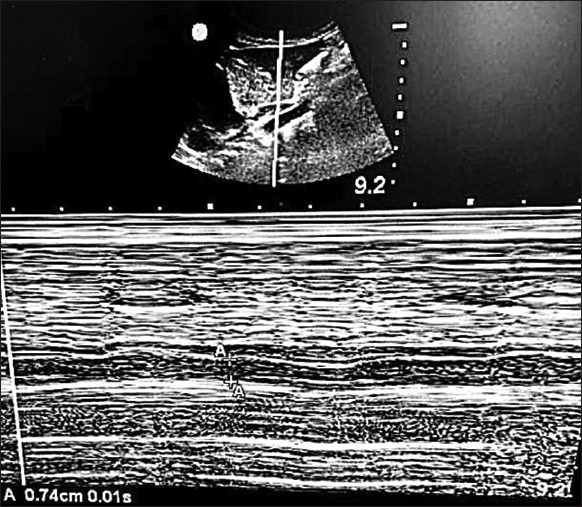

Material and methods: A single-center prospective observational study was conducted involving pediatric patients aged 1-12 years undergoing elective surgery. Ethical approval and written consent were obtained, with exclusions for major cardiovascular issues. Ultrasound measurements of IVC and aorta were performed by two observers during spontaneous and controlled ventilation in the subxiphoid transabdominal long-axis view. Reliability was assessed through statistical analyses, including the intraclass correlation coefficient and Bland-Altman analysis.

Results: Mean values of IVC and aorta diameters were summarized for both observers during different ventilation modes. The intraclass correlation coefficient indicated excellent to good agreement between the observers for both spontaneous and controlled ventilation scenarios. Bland-Altman analysis revealed no fixed or proportional errors, confirming the reliability of the measurements.